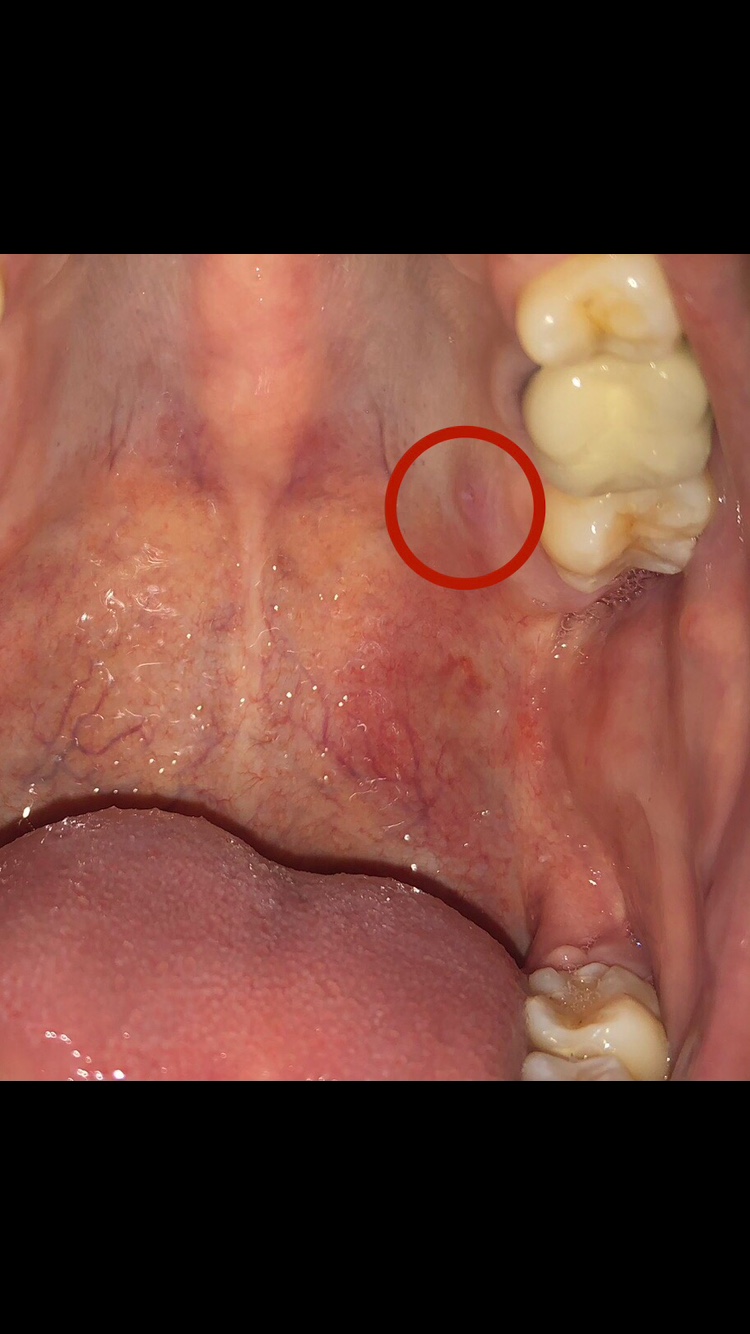

ใครเคยเป็นแบบนึ้บ้างค่ะ มันคืออะไรค่ะ เป็นมา เดือนกว่าแล้ว ช่วงแรกไม่ปวด หลังๆมีอาการปวดบ้าง แต่ไม่มีอาการปวดฟันนะคะ